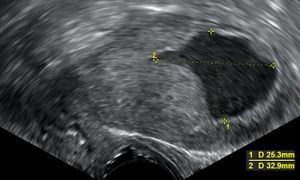

- التصوير فائق الصوت عبر المهبل